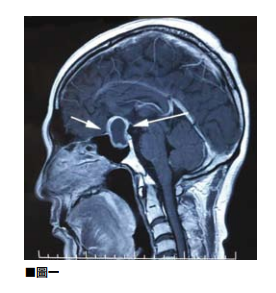

三叉神經痛和舌咽神經痛綜合症